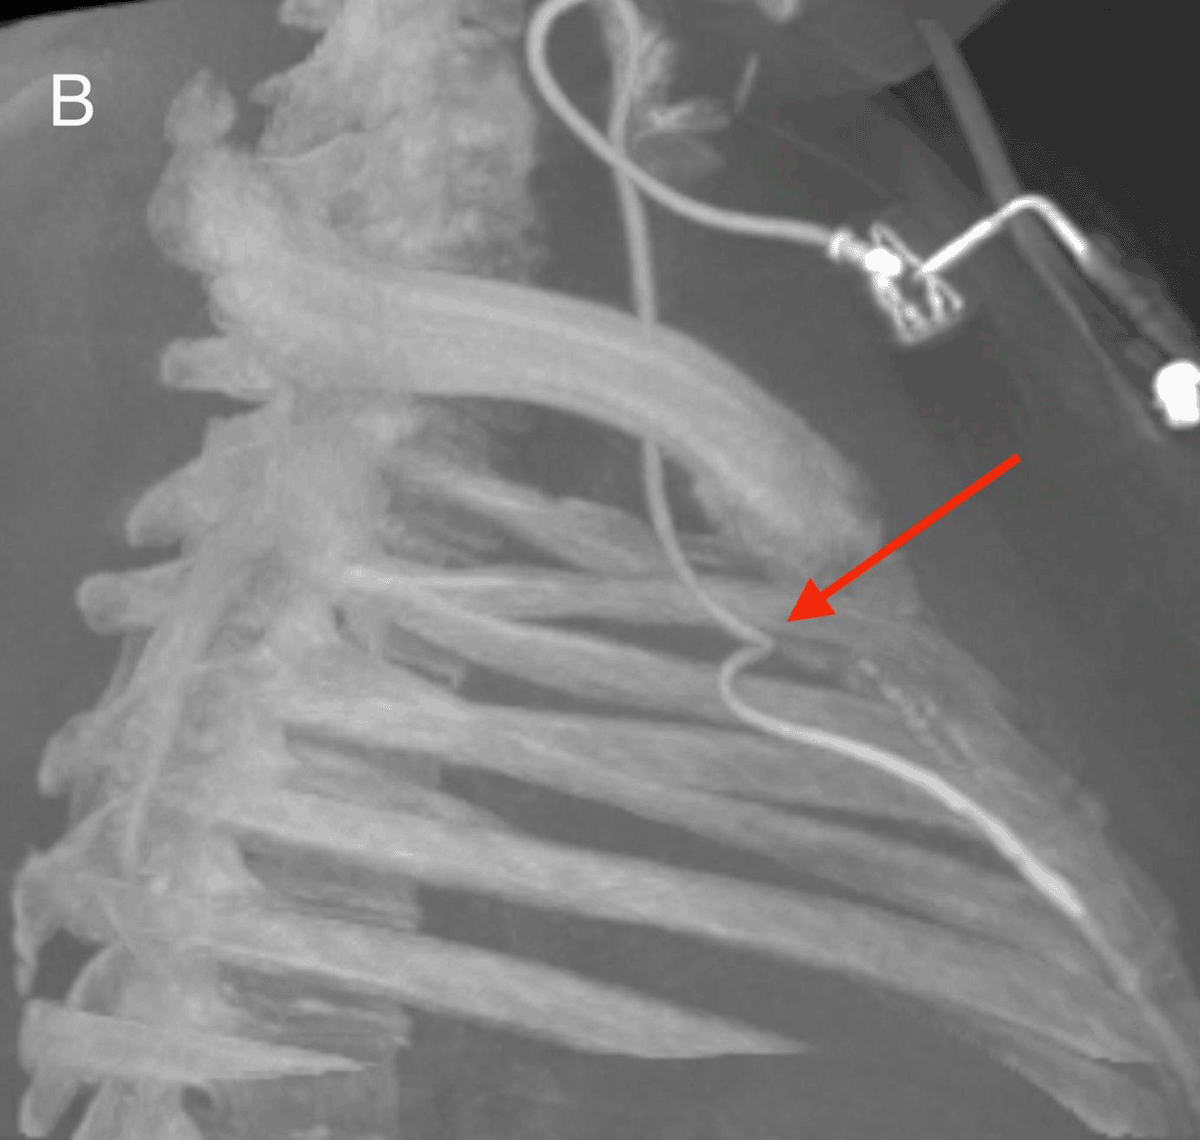

After re-assessment of the initial chest radiograph, a C-arm cone-beam computed tomography was ordered and demonstrated the incorrect anterior positioning of the last centimeters of the catheter, presumably in the right internal thoracic vein (arrow Figure B). Opacification by iodine contrast injection through the CVP showed thrombosis around the tip of the catheter with backflow to the brachiocephalic vein before antegrade flow (arrows, Figure C, the white dotted line shows the catheter through ostium of the right internal thoracic vein). Via femoral vein access, we created a loop around the CVP catheter in the left brachiocephalic vein with a guidewire and a snare, allowing for removal of the catheter by traction from the internal thoracic vein.

Figure B